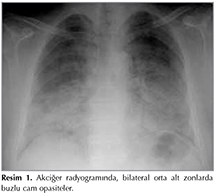

Kırk beş yaşında erkek hasta, ara ara olan ?ks?r?k ve son bir aydır artış g?steren nefes darlığı şikayetleri ile başvurdu. ?zge?mişinde 30 paket yılı sigara i?me ve inşaat iş?iliği (taş kesme) ?yk?s? mevcuttu. Solunum sistemi ve sistemik muayenesinde patolojik bulgu saptanmadı. Akciğer radyogramında, bilateral orta alt zonlarda buzlu cam opasitesi izlendi (Resim 1). Laboratuvar tetkiklerinde sedimentasyon hızı 3 mm/h, l?kosit 8.700 (x103/mL), hemoglobin 14.3 g/dL, trombosit 278.000 (x103/mL), LDH 575 U/L, CRP 0.3 mg/dL, pro-BNP 20.5 pg/mL bulundu. Hepatit markerları (HBV, HCV, HIV) negatifti. arteryel kan gazında istirahat halinde pH: 7.44, paCO2: 36.6 mmHg, paO2: 65.2 mmHg, SO2: %92.4, Alveoler-arteriyal oksijen gradienti (PA-aO2) 38.7 idi. Hafif eforla oksijensiz periferik SpO2 %84 olması nedeniyle 6 dakika y?r?me testi yapılamadı. Solunum fonksiyon testinde FEV1/FVC: %92, FEV1: %109 (3.57 litre), FVC: %91 (3.87 litre) ve akciğer karbonmonoksit dif?zyon testinde DLCO: %49 olarak saptandı. Y?ksek rezolusyonlu bilgisayarlı tomografide (YRBT) her iki akciğer parankiminde yaygın buzlu cam ve interlob?ler septal kalınlaşmalar g?zlendi (Resim 2). Dif?z parankimal akciğer hastalığı etyolojisi a?ısından hastaya bronkoskopi yapıldı ve sağ orta lob medial segmentten BAL yapıldı. BAL sıvısının beyaz renkte s?t g?r?n?m?nde olduğu izlendi. BAL histopatolojik incelemesinde, zeminde PAS (+) boyanan gran?ler materyal izlendiği, transbronşiyal biyopside (TBB) bu materyalin alveoler l?meni doldurduğu, g?r?n?m?n alveoler proteinozis i?in uyumlu olduğu raporlandı (Resim 3).

Resim 1